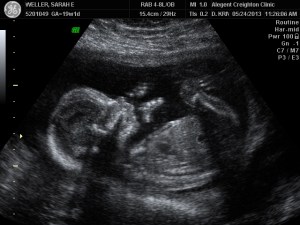

BABY BOY_16Why? Because when you are a pregnant, you are intimately aware that you are part of a great mystery. Every fiber of your being lets you know that you are a vessel in a bigger story. An act of creation is taking place, and, sorry, you have little to nothing to do with it.